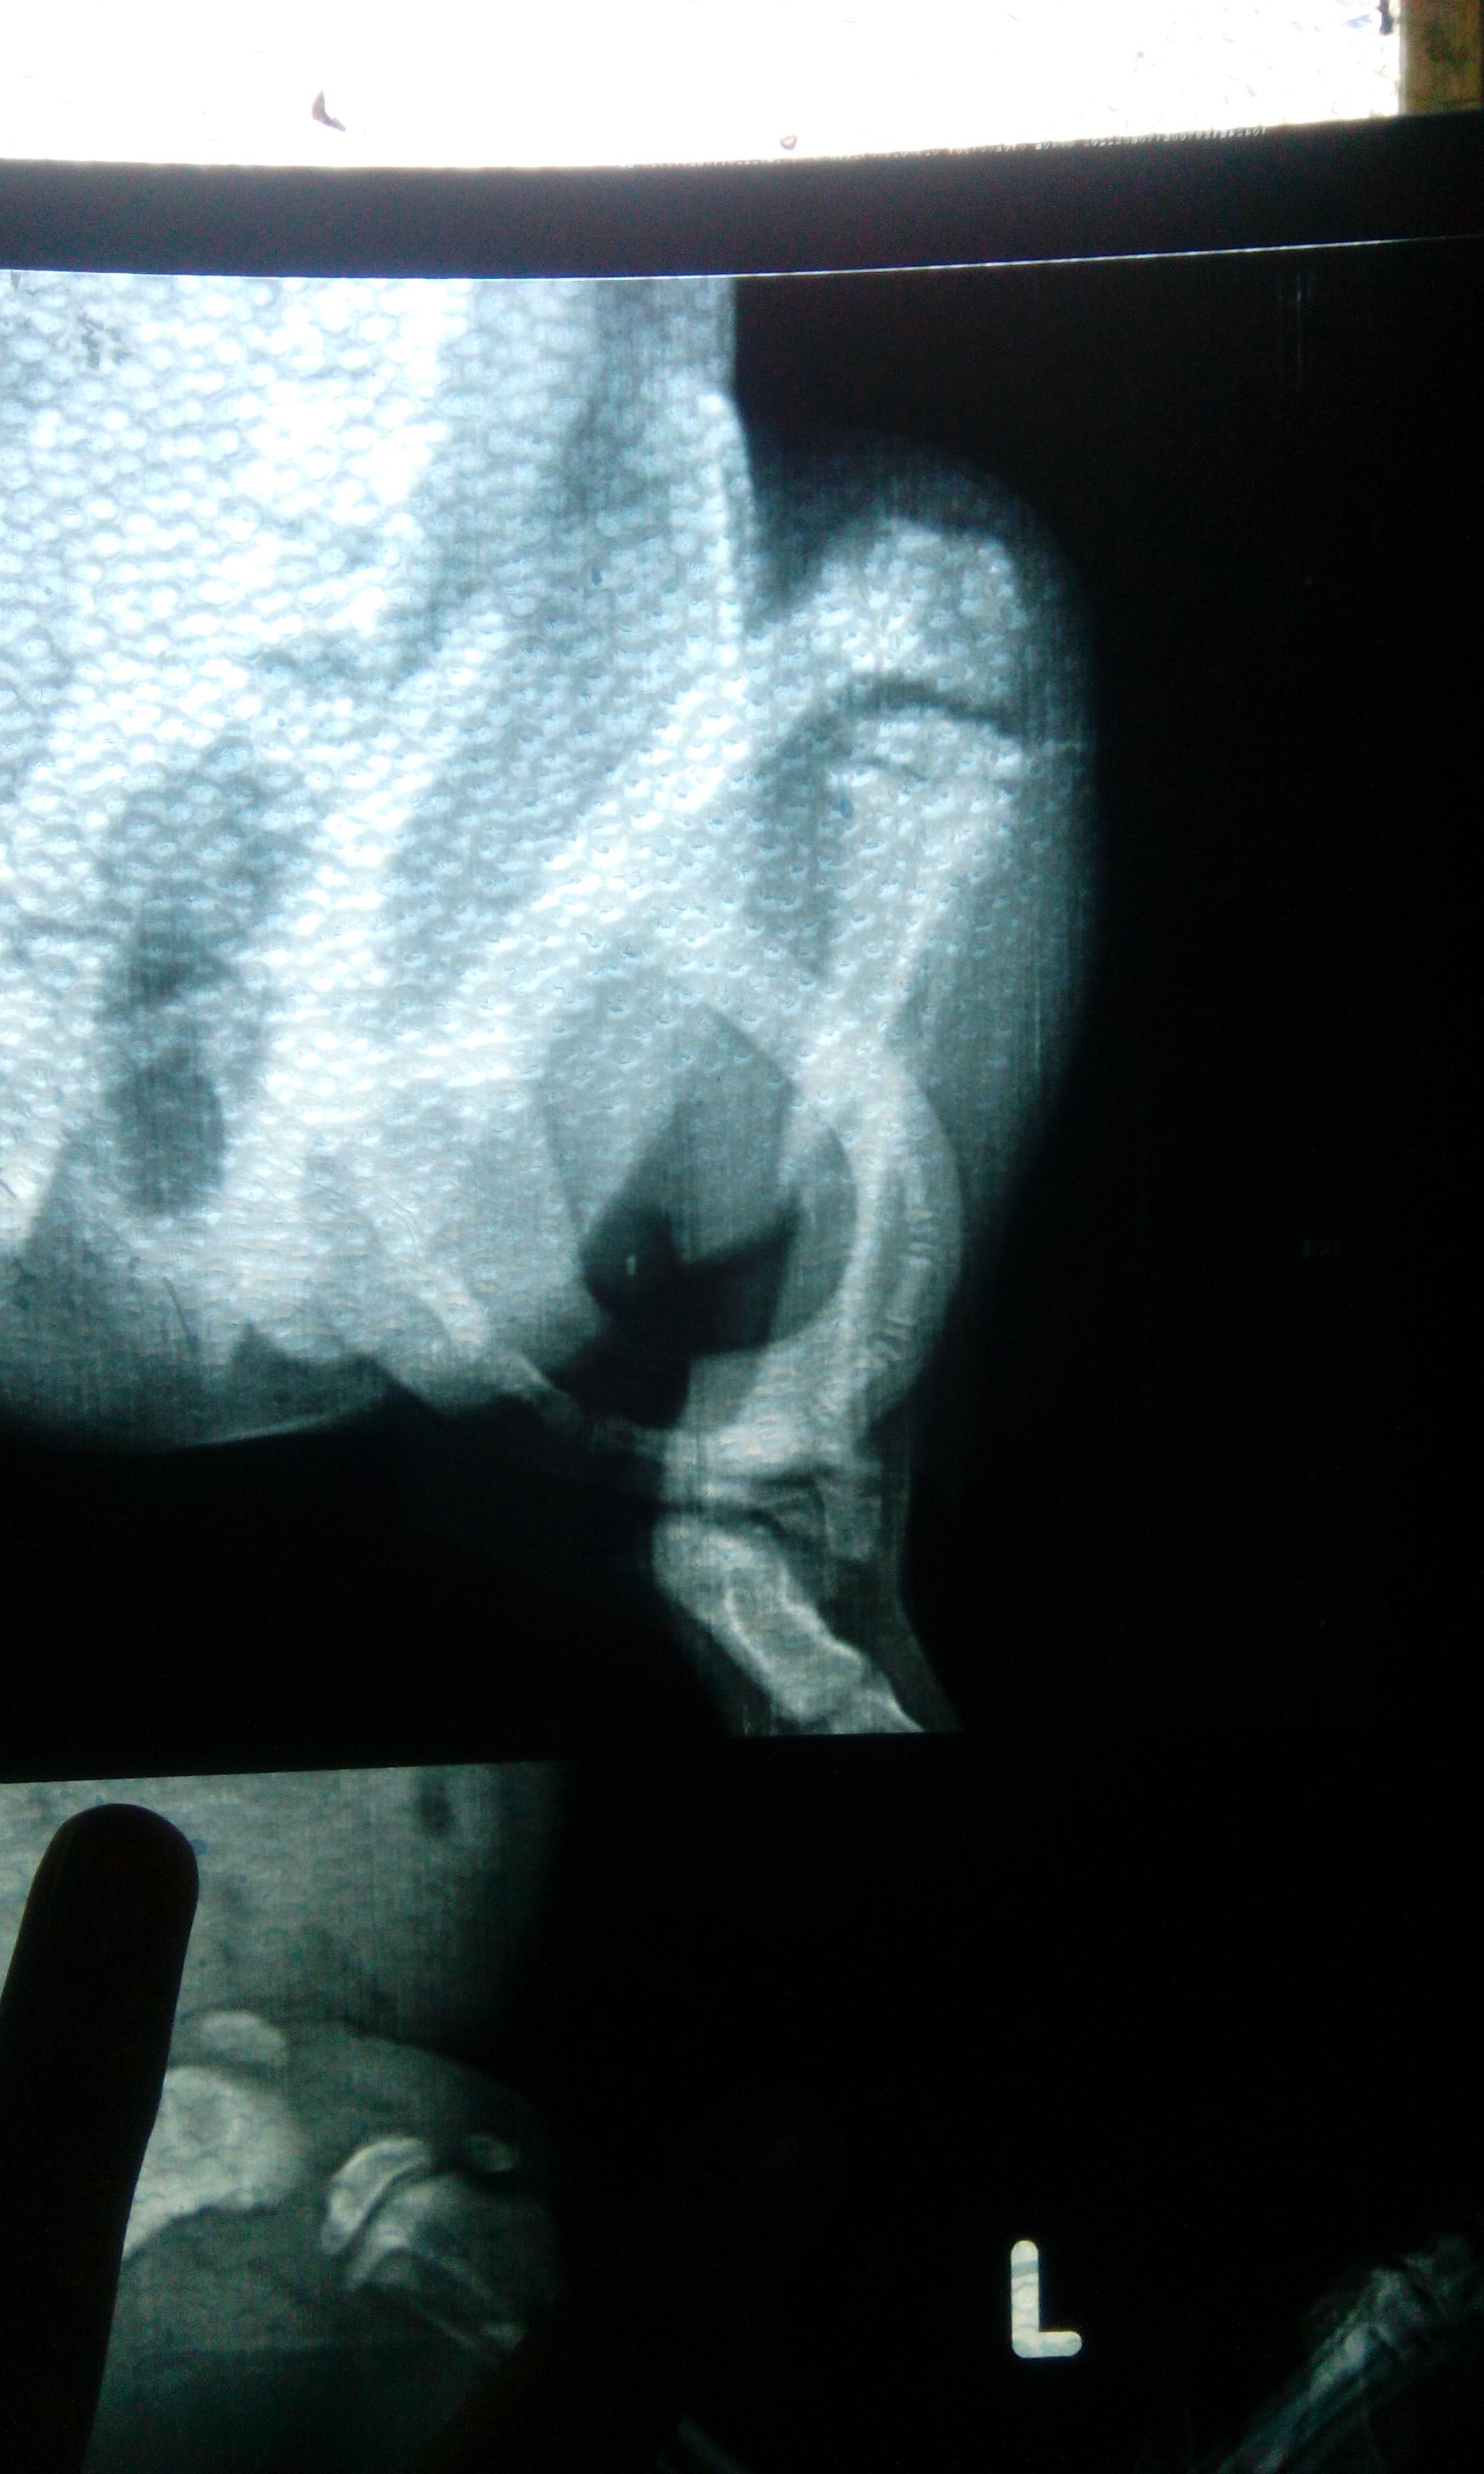

My pug, 2 months old, slipped from my hands and broke his left lower limb. I took 3 different vet consultations all in vain. His plasters slip off and its very hard to put up something that keeps his leg straight. We confined him to a little cage to not let him run. He is keeping his foot on the ground now after 7 days from the injury and we aren't tying up any bandages buy are giving him supplements. Will he be able to walk again without any deformity?

Ouch, poor Scooter! It looks like a painful break, and unfortunately only time will tell if his leg will heal properly or not. Keeping him confined to a cage is a good idea to make him rest fully, and I would only take him out to go to the bathroom and then bring him right back inside to the cage. If you can't keep the leg immobilized, then it may not grow back correctly but again only time will tell. I'm not sure what supplements you are giving him, but please be very careful when doing that; in fact, I wouldn't recommend it unless your vet told you to give them to Scooter. Too many supplements in a growing puppy will cause health problems such as developmental abnormalities from too much calcium. That's why it's never recommended to give a puppy vitamins. If your vet hasn't told you to give these supplements, I would check with them that it's ok for Scooter to receive them.